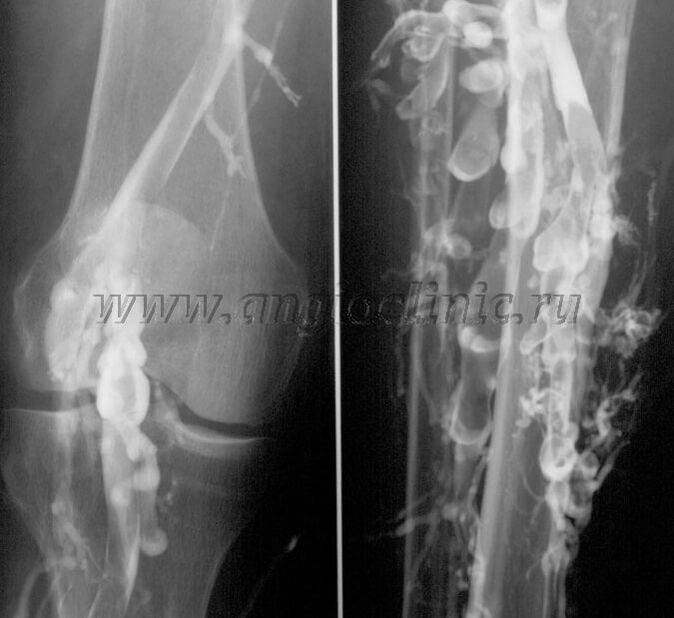

Contrast venography

Usually, ultrasound is enough to fully diagnose venous pathology, but in some cases it is necessary to study the relationship between the state of the deep and superficial venous systems, especially in cases of recurrent varicose veins and secondary varicose veins.

To solve these problems, contrast x-ray examination is used.The saphenous vein is punctured and contrast medium is injected.Movement of the contrast is observed on the screen of the X-ray machine and all necessary tests and projections are performed.Currently, venography for varicose veins is rarely used.